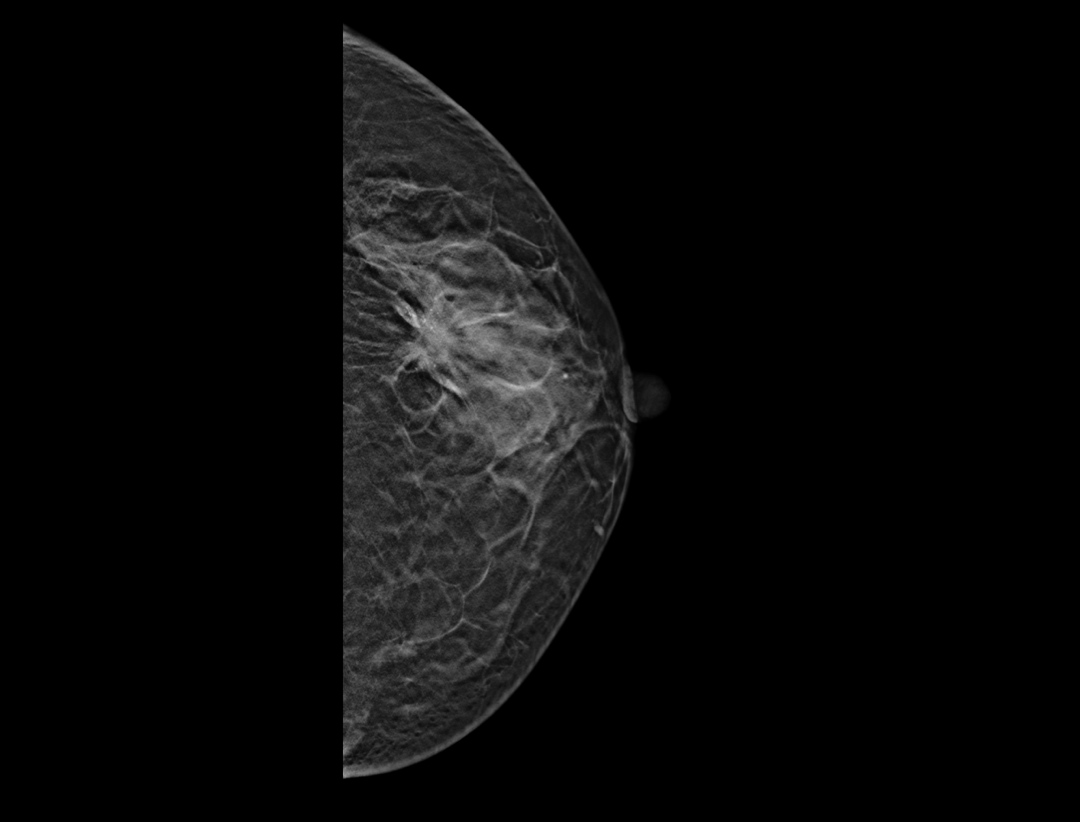

自定义层厚融合

更精细观察肿块及钙化簇的空间分布。